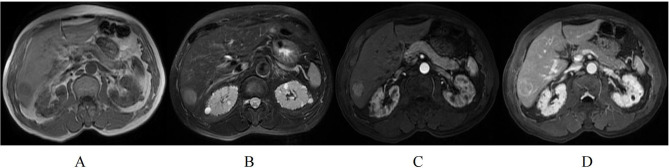

Results: The median RFS for the 134 patients was 45.7 months, with 41.8% of patients experiencing tumor recurrence after hepatectomy. Univariate Cox regression analysis identified hepatitis Be antigen (HBeAg) positivity, tumor size, tumor growth subtype, non-peripheral washout, nodule-in-nodule architecture, mosaic architecture, and intratumoral arteries as significant risk factors for RFS. Multivariate Cox regression analysis revealed that HBeAg positive, tumor growth subtype, non-peripheral washout, mosaic architecture, and internal arteries were independent prognostic factors for RFS in patients with solitary HCC without MVI. The nomogram based on these variables demonstrated good predictive accuracy, with concordance indices (C-index) of 0.740 and 0.701 in the training and validation cohorts, respectively. Additionally, patients in the high-risk group exhibited significantly lower RFS compared to those in the low-risk group.